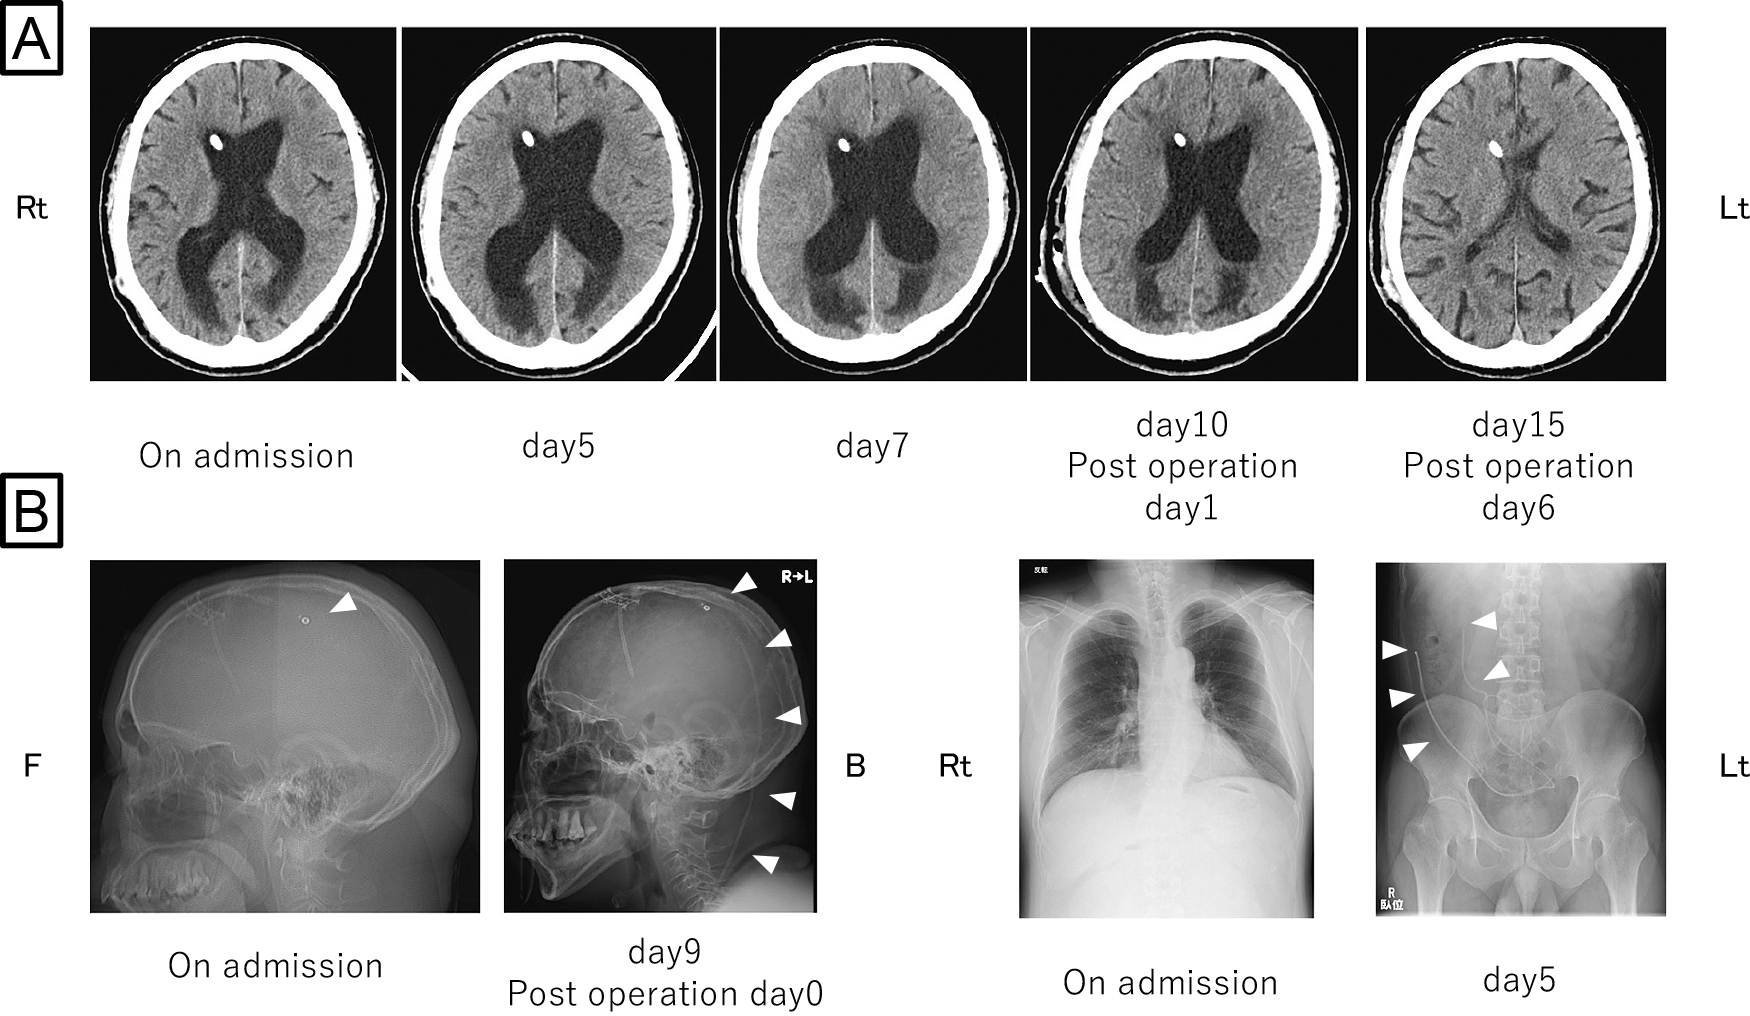

直接経口抗凝固薬内服にもかかわらず脳梗塞を発症した心房細動患者に対する経皮的左心耳閉鎖術:症例報告

Percutaneous left atrial appendage closure for atrial fibrillation-related ischemic stroke despite direct oral anticoagulation: a case report

川端 健新, 江頭 柊平, 村松 恭祐, 逸見 文昭, 宇羽野 恵, 小西 明範, 大森 奈美, 山口 徹雄, 児玉 隆秀, 上坂 義和

Kenshin Kawabata, Shuhei Egashira, Kyosuke Muramatsu, Fumiaki Henmi, Megumi Ubano, Akinori Konishi, Nami Omori, Tetsuo Yamaguchi, Takahide Kodama, Yoshikazu Uesaka

2026/02/13